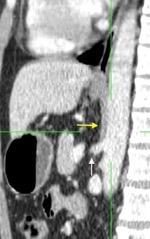

Parte lumbar: 1.Ligamentos arcuatos medial y lateral

2. Cruras conectadas a vértebras lumbares y discos. L1-3 a la dcha. L1-2 a la izda.

Cruras conectadas por encima del tronco celíaco por ligamento fibroso arcuato medial. Panicek DM et al. Radiographics. 1998

Las fibras más bajas de las cruras se funden con las de las vainas de los músculos psoas, acotando un espacio llamado “Espacio abierto de la vaina del psoas”, que comunica las cavidades torácica y abdominal.

Panda A et al. “Straddling Across Boundaries”. Thoracoabdominal Lesions: Spectrum and Pattern Approach. Curr Probl Diagn Radiol, 2015 /Restrepo CS et al. The diaphragmatic crura and retrocrural space: normal imaging appearance, variants, and pathologic conditions. Radiographics 2008